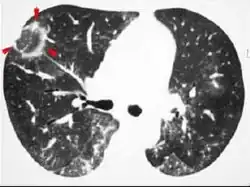

CT scan showing cryptogenic organizing pneumonia (biopsy-proven)

The reversed halo sign is seen in about 20% of individuals with COP.[18]

The chest x-ray is distinctive with features that appear similar to an extensive pneumonia, with both lungs showing widespread white patches. The white patches may seem to migrate from one area of the lung to another as the disease persists or progresses. Computed tomography (CT) may be used to confirm the diagnosis. Often the findings are typical enough to allow the doctor to make a diagnosis without ordering additional tests.[19] To confirm the diagnosis, a doctor may perform a lung biopsy using a bronchoscope. Many times, a larger specimen is needed and must be removed surgically.

Plain chest radiography shows normal lung volumes, with characteristic patchy unilateral or bilateral consolidation. Small nodular opacities occur in up to 50% of patients and large nodules in 15%. On high resolution computed tomography, airspace consolidation with air bronchograms is present in more than 90% of patients, often with a lower zone predominance. A subpleural or peribronchiolar distribution is noted in up to 50% of patients. Ground glass appearance or hazy opacities associated with the consolidation are detected in most patients.

Unusual presentations of organizing pneumonia

While patchy bilateral disease is typical, there are unusual variants of organizing pneumonia where it may appear as multiple nodules or masses. One rare presentation, focal organizing pneumonia, may be indistinguishable from lung cancer based on imaging alone, requiring biopsy or surgical resection to make the diagnosis.[20]